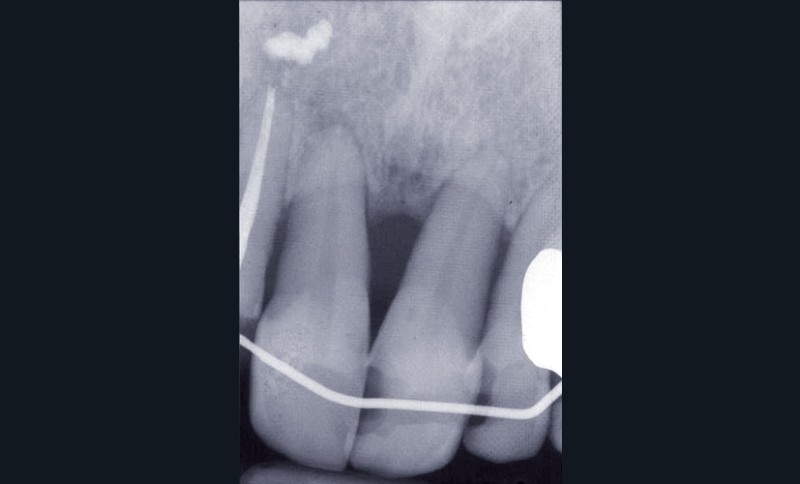

Les examens cliniques et radiographiques montrent une parodontite chronique généralisée (fig. 1a à m).

Nous décidons d’entreprendre une thérapeutique initiale parodontale classique dans tous les secteurs, y compris l’extraction de 24, un bridge de 45 à 48 avec 46 en pontique, un bridge complet de contention de 17 à 27 sur 11 piliers dentaires et une greffe épithélio-conjonctive sur 31. Cette dernière ne sera jamais réalisée. Le bridge maxillaire permettra de réduire le surplomb antérieur et d’améliorer le sourire de la patiente, ce qui constitue l’une de ses demandes.